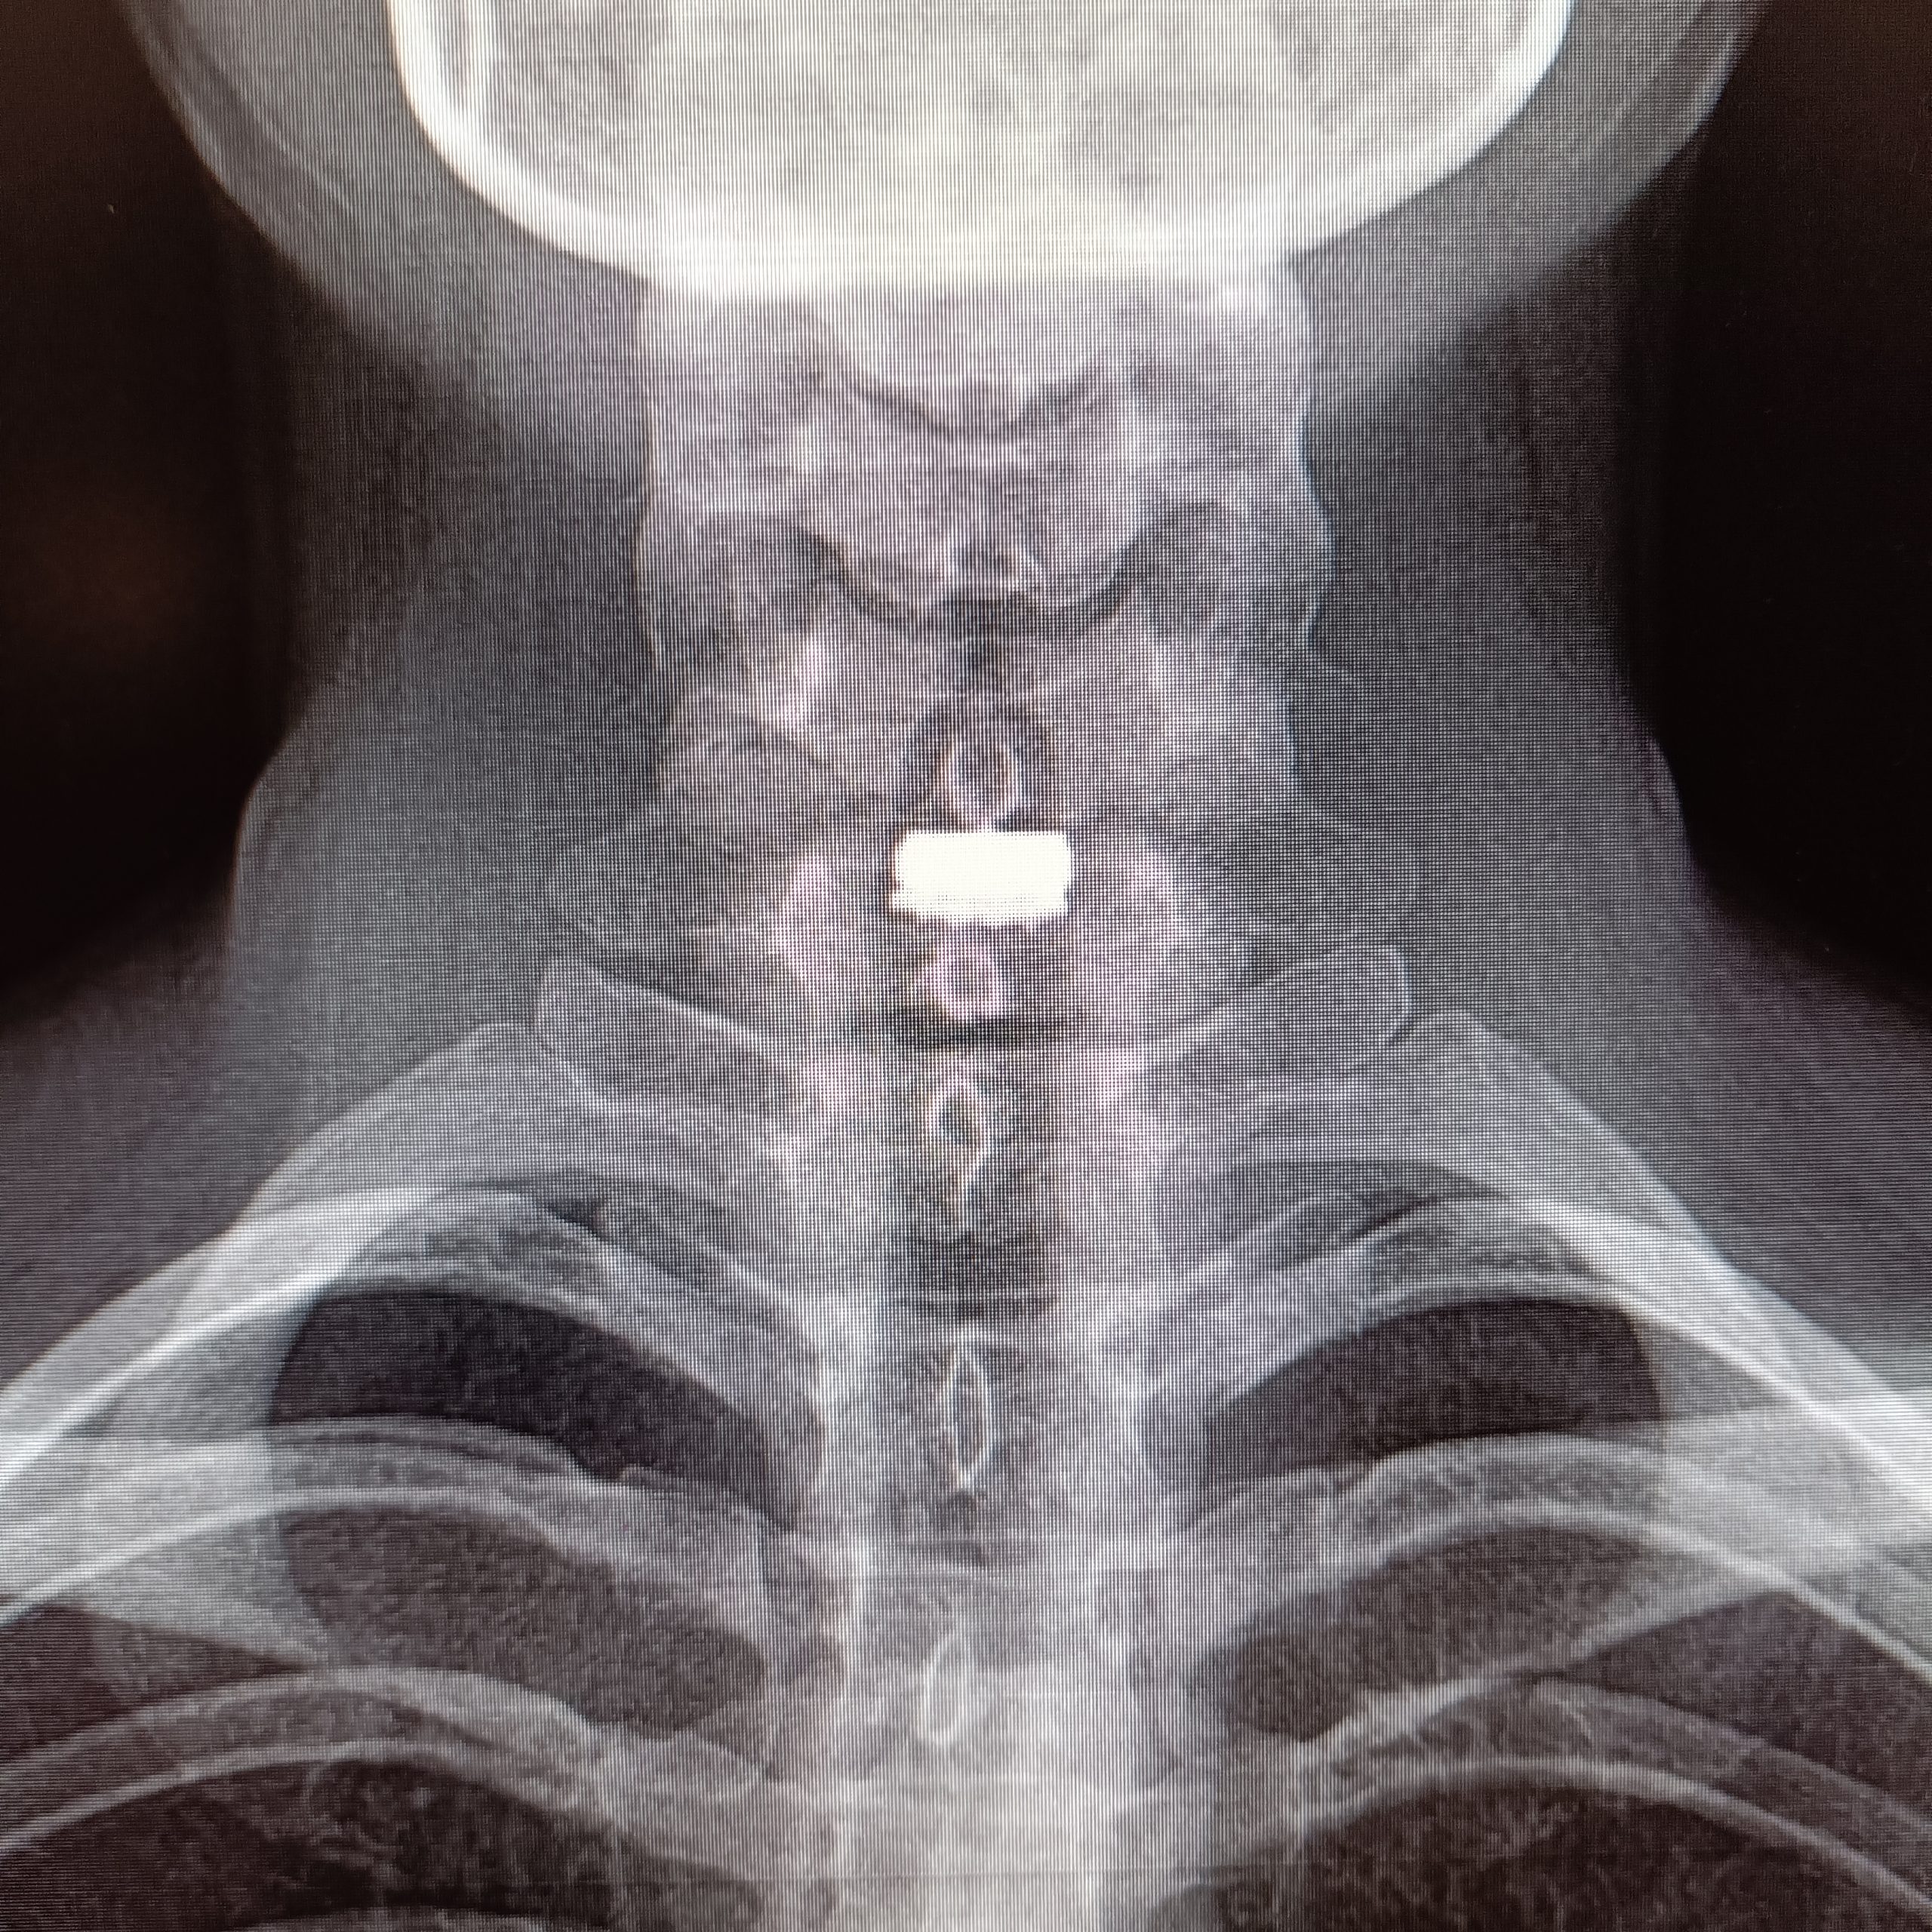

Günümüzde boyun fıtığı cerrahisinde hem erken dönemde hareket kabiliyetinin kısıtlanmadan en doğal şekliyle korunması hem de söz ettiğimiz “komşu segment hastalığı”nın önlenmesi açısından tercih edilen yöntem servikal disk protezleri. Bu protezler vücudun kabul ettiği, herhangi bir alerjik reaksiyon yaratmayan özel plastik ve seramik alaşımlar ile titanyum gibi hafif ve çok dayanıklı malzemelerden üretiliyor.

Yeditepe Üniversitesi Koşuyolu Hastanesi’nde servikal disk protezi kullanılarak başarı oranı yüksek boyun fıtığı ameliyatları yapıyor. Hastalar ameliyat sonrası en kısa zamanda sağlıklarına kavuşup günlük hayatlarına dönme fırsatı buluyor. Ayrıca boynun kendi doğal hareketlerini, esnekliğini ve yük taşıma kapasitesini koruyan servikal disk proteziyle yapılan ameliyatlarla tedavi edilen bölgenin alt ve üstündeki disklerin sağlığı da korunmuş oluyor.